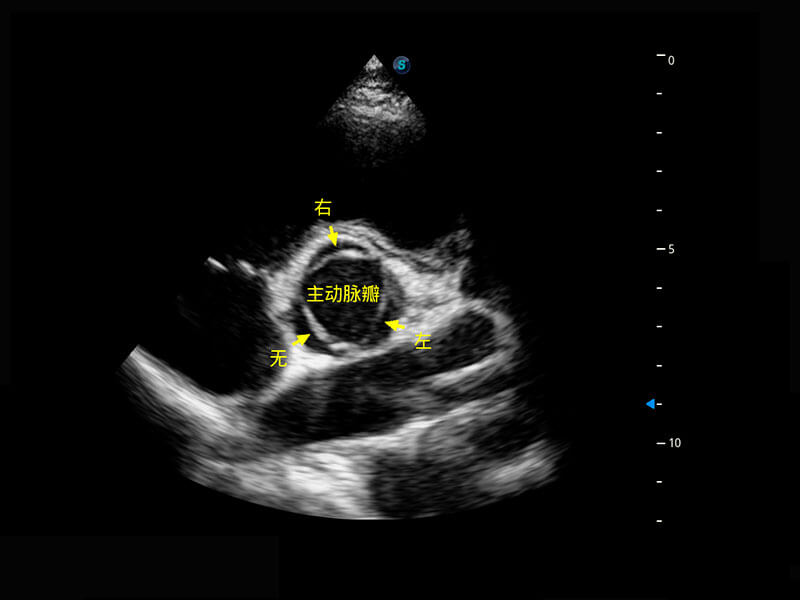

胎心筛查

P60搭载一系列胎儿心脏成像技术,实现精细的胎儿心脏评估。

• 胎心容积成像